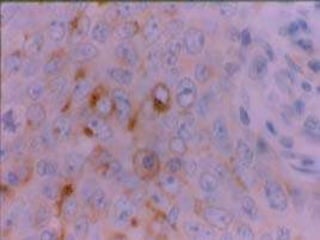

Melanoma maligno

 Edad: 32-92 años

 Cualquier sitio de la

mucosa oral

 Predominio en encía

maxilar y paladar duro

 Mácula pigmentada

rodeada por el tumor: 75%

 Nodular puro: 25%.

Amelánicos 14%

 Metástasis linfáticas y

hematógenas

 Enf. avanzada: pobre Px.

Melanoma maligno  Edad:32-92 años  Cualquier sitio de la mucosa oral  Predominio en encía maxilar y paladar duro  Mácula pigmentada rodeada por el tumor: 75%  Nodular puro: 25%. Amelánicos 14%  Metástasis linfáticas y hematógenas  Enf. avanzada: pobre Px.